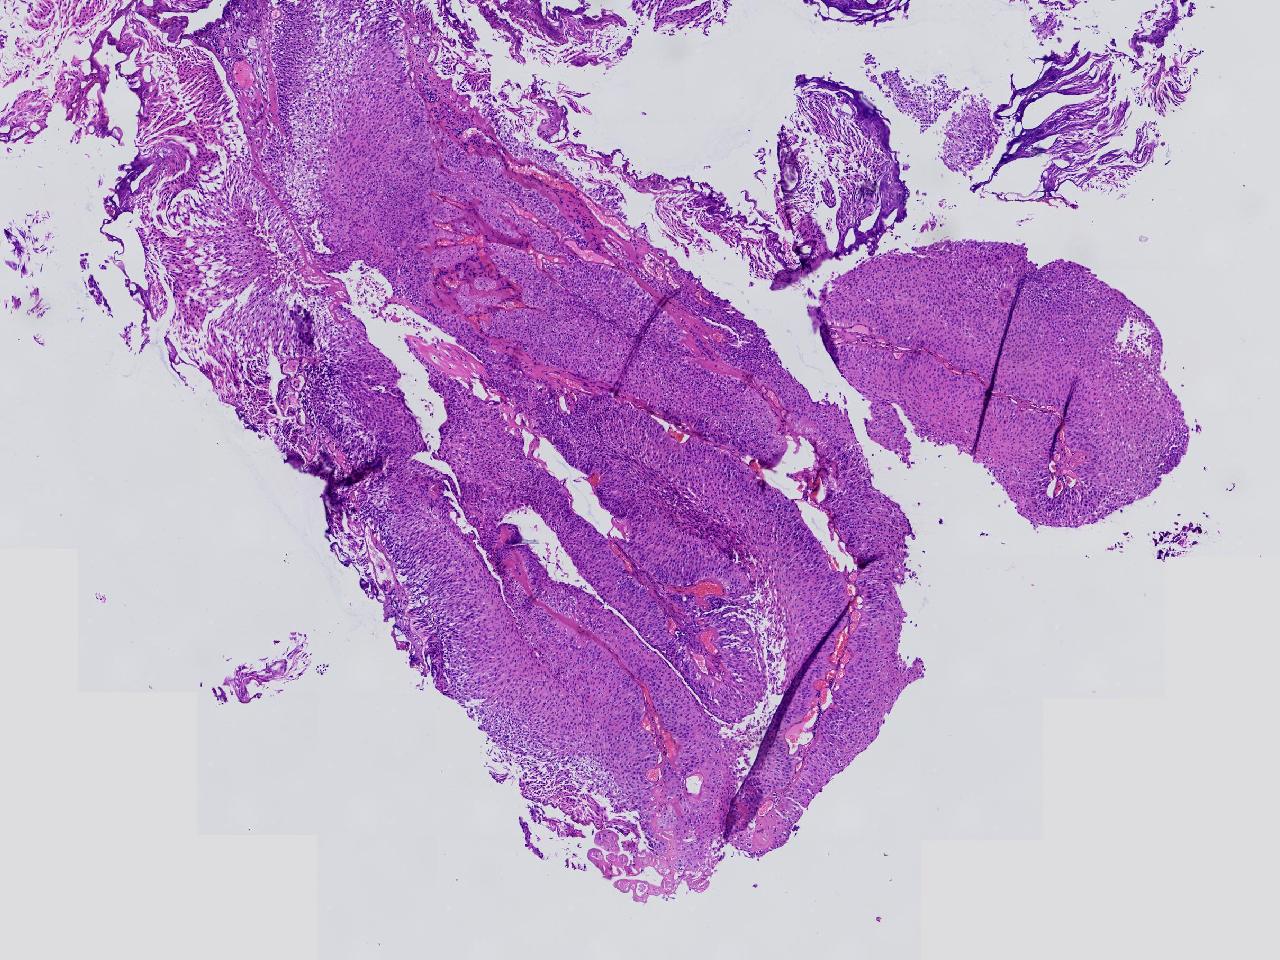

男,79岁,膀胱肿物。

膀胱肿物

灰白色不整形软组织多块,2X1X1厘米。

考虑:乳头状尿路上皮癌

考虑低级别,非浸润。

乳头状尿路上皮癌,低级别。

这几张图片上没有看到明确的浸润。